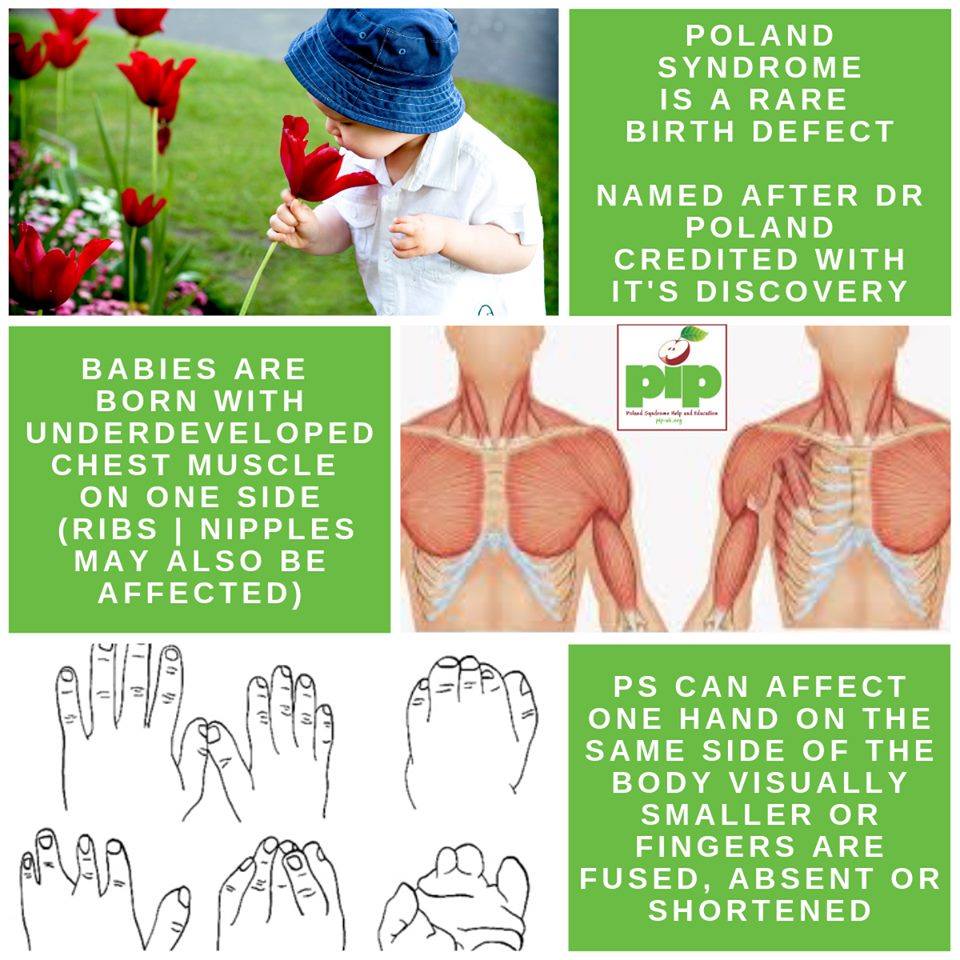

radiomed.ruPin On Poland Syndrome | News

radiomed.ruPin On Poland Syndrome | News

www.pinterest.co.ukPoland Syndrome / What Is Poland Syndrome Causes Treatment Surgery

www.pinterest.co.ukPoland Syndrome / What Is Poland Syndrome Causes Treatment Surgery

radiopaedia.orgPoland Syndrome Awareness Graphic By The Design Factory · Creative Fabrica

radiopaedia.orgPoland Syndrome Awareness Graphic By The Design Factory · Creative Fabrica

www.creativefabrica.comA Poland Syndrome Charity Site - Pip-uk.org

www.creativefabrica.comA Poland Syndrome Charity Site - Pip-uk.org

pip-uk.orgpoland syndrome pip charity our

pip-uk.orgpoland syndrome pip charity our

Poland syndrome description stock photo. Healthjade anomaly. Living with poland syndrome. how to live with poland syndrome?